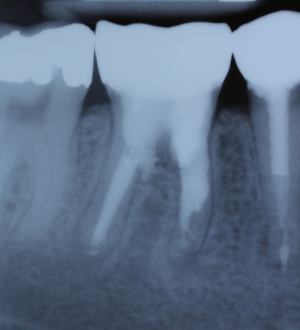

Eine absolute Extraktionsindikation stellt die Wurzellängsfraktur bei einwurzeligen Zähnen dar. Differenzierter zu betrachten ist die Wurzellängsfraktur eines mehrwurzeligen Zahnes. Bei entsprechend günstigen Voraussetzungen kann mitunter auch die Option einer Hemisektion in Betracht gezogen werden. In die Entscheidungsfindung sollten auch immer Überlegungen zur langfristigen Planung einfließen. Die prothetische Wertigkeit eines Molaren ist beispielsweise durch die Entfernung einer Wurzel deutlich herabgesetzt. Klinisch imponiert bei Längsfrakturen der sogenannte „Kamineffekt“. Bei zirkulär sonst unauffälligen Sondierungstiefen fällt man entlang des Frakturverlaufs mit der Messsonde in den osteolytisch entstandenen „Kamin“ (Abb. 13). Auch im hier dargestellten Fall (Abb. 16) war nach Auswertung aller relevanten Aspekte (Ursache, Prognose, langfristige prothetische Planung) die frühzeitige Extraktion Mittel der Wahl um die Voraussetzungen für eine anschließende Implantation nicht negativ zu beeinflussen.